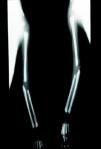

En cuanto a la afección del sistema nervioso, las manifestaciones tempranas corresponden a la meningitis y la hidrocefalia, que pueden dejar como secuela retardo mental o psicomotriz, ya sea leve o severo. La afectación pulmonar más conocida es la neumonía con patrón intersticial proliferativo o neumonía alba48. Hay afección renal y, aun en ausencia de manifestaciones neurológicas, pueden existir alteraciones en el líquido cefalorraquídeo (LCR). La mayoría de los niños con SC aparentemente asintomáticos pueden manifestar alteraciones radiográficas en forma de osteocondritis o pericondritis, periostitis y osteomielitis diafisaria (figs. 12 y 13). En ocasiones las lesiones óseas pueden ser dolorosas con destrucción ósea o tener fracturas superpuestas, dando lugar a seudoparálisis del miembro afectado, más conocido como seudoparálisis de Parrot48,49.